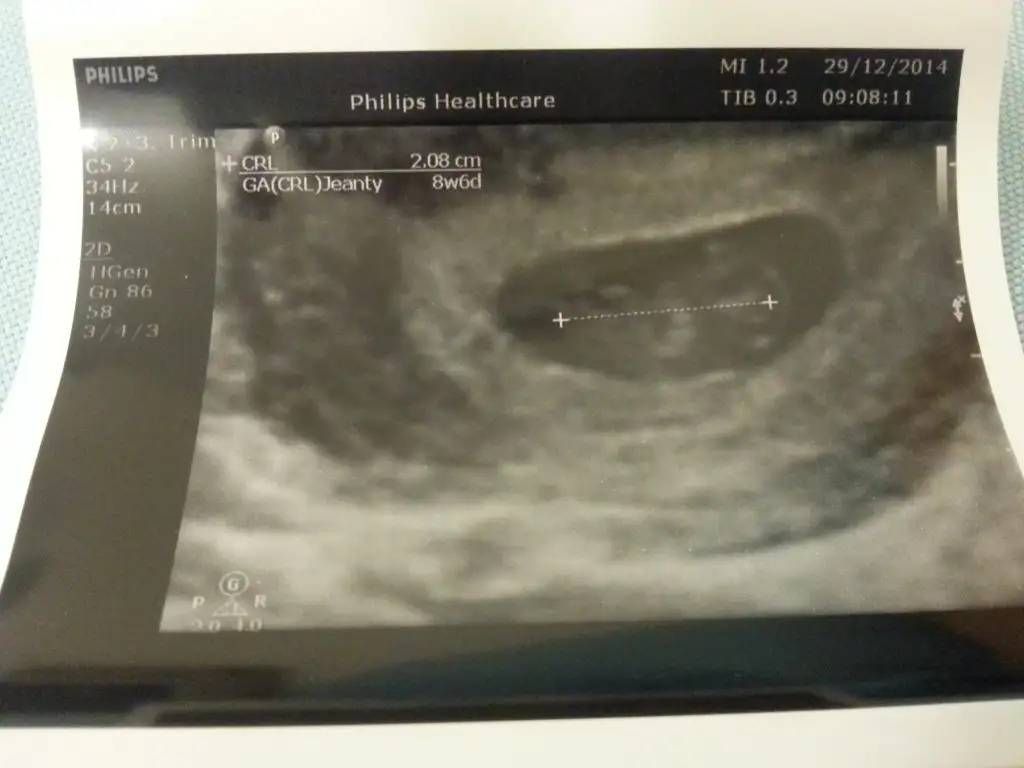

Benim doktorum bebek büyüdükçe boyunu ölçüp ultrason cihazina hesaplatmaya basladi.. ornegi ekledim

Eklentiler

• 20141229_184830.webp

23,1 KB · Görüntüleme: 72